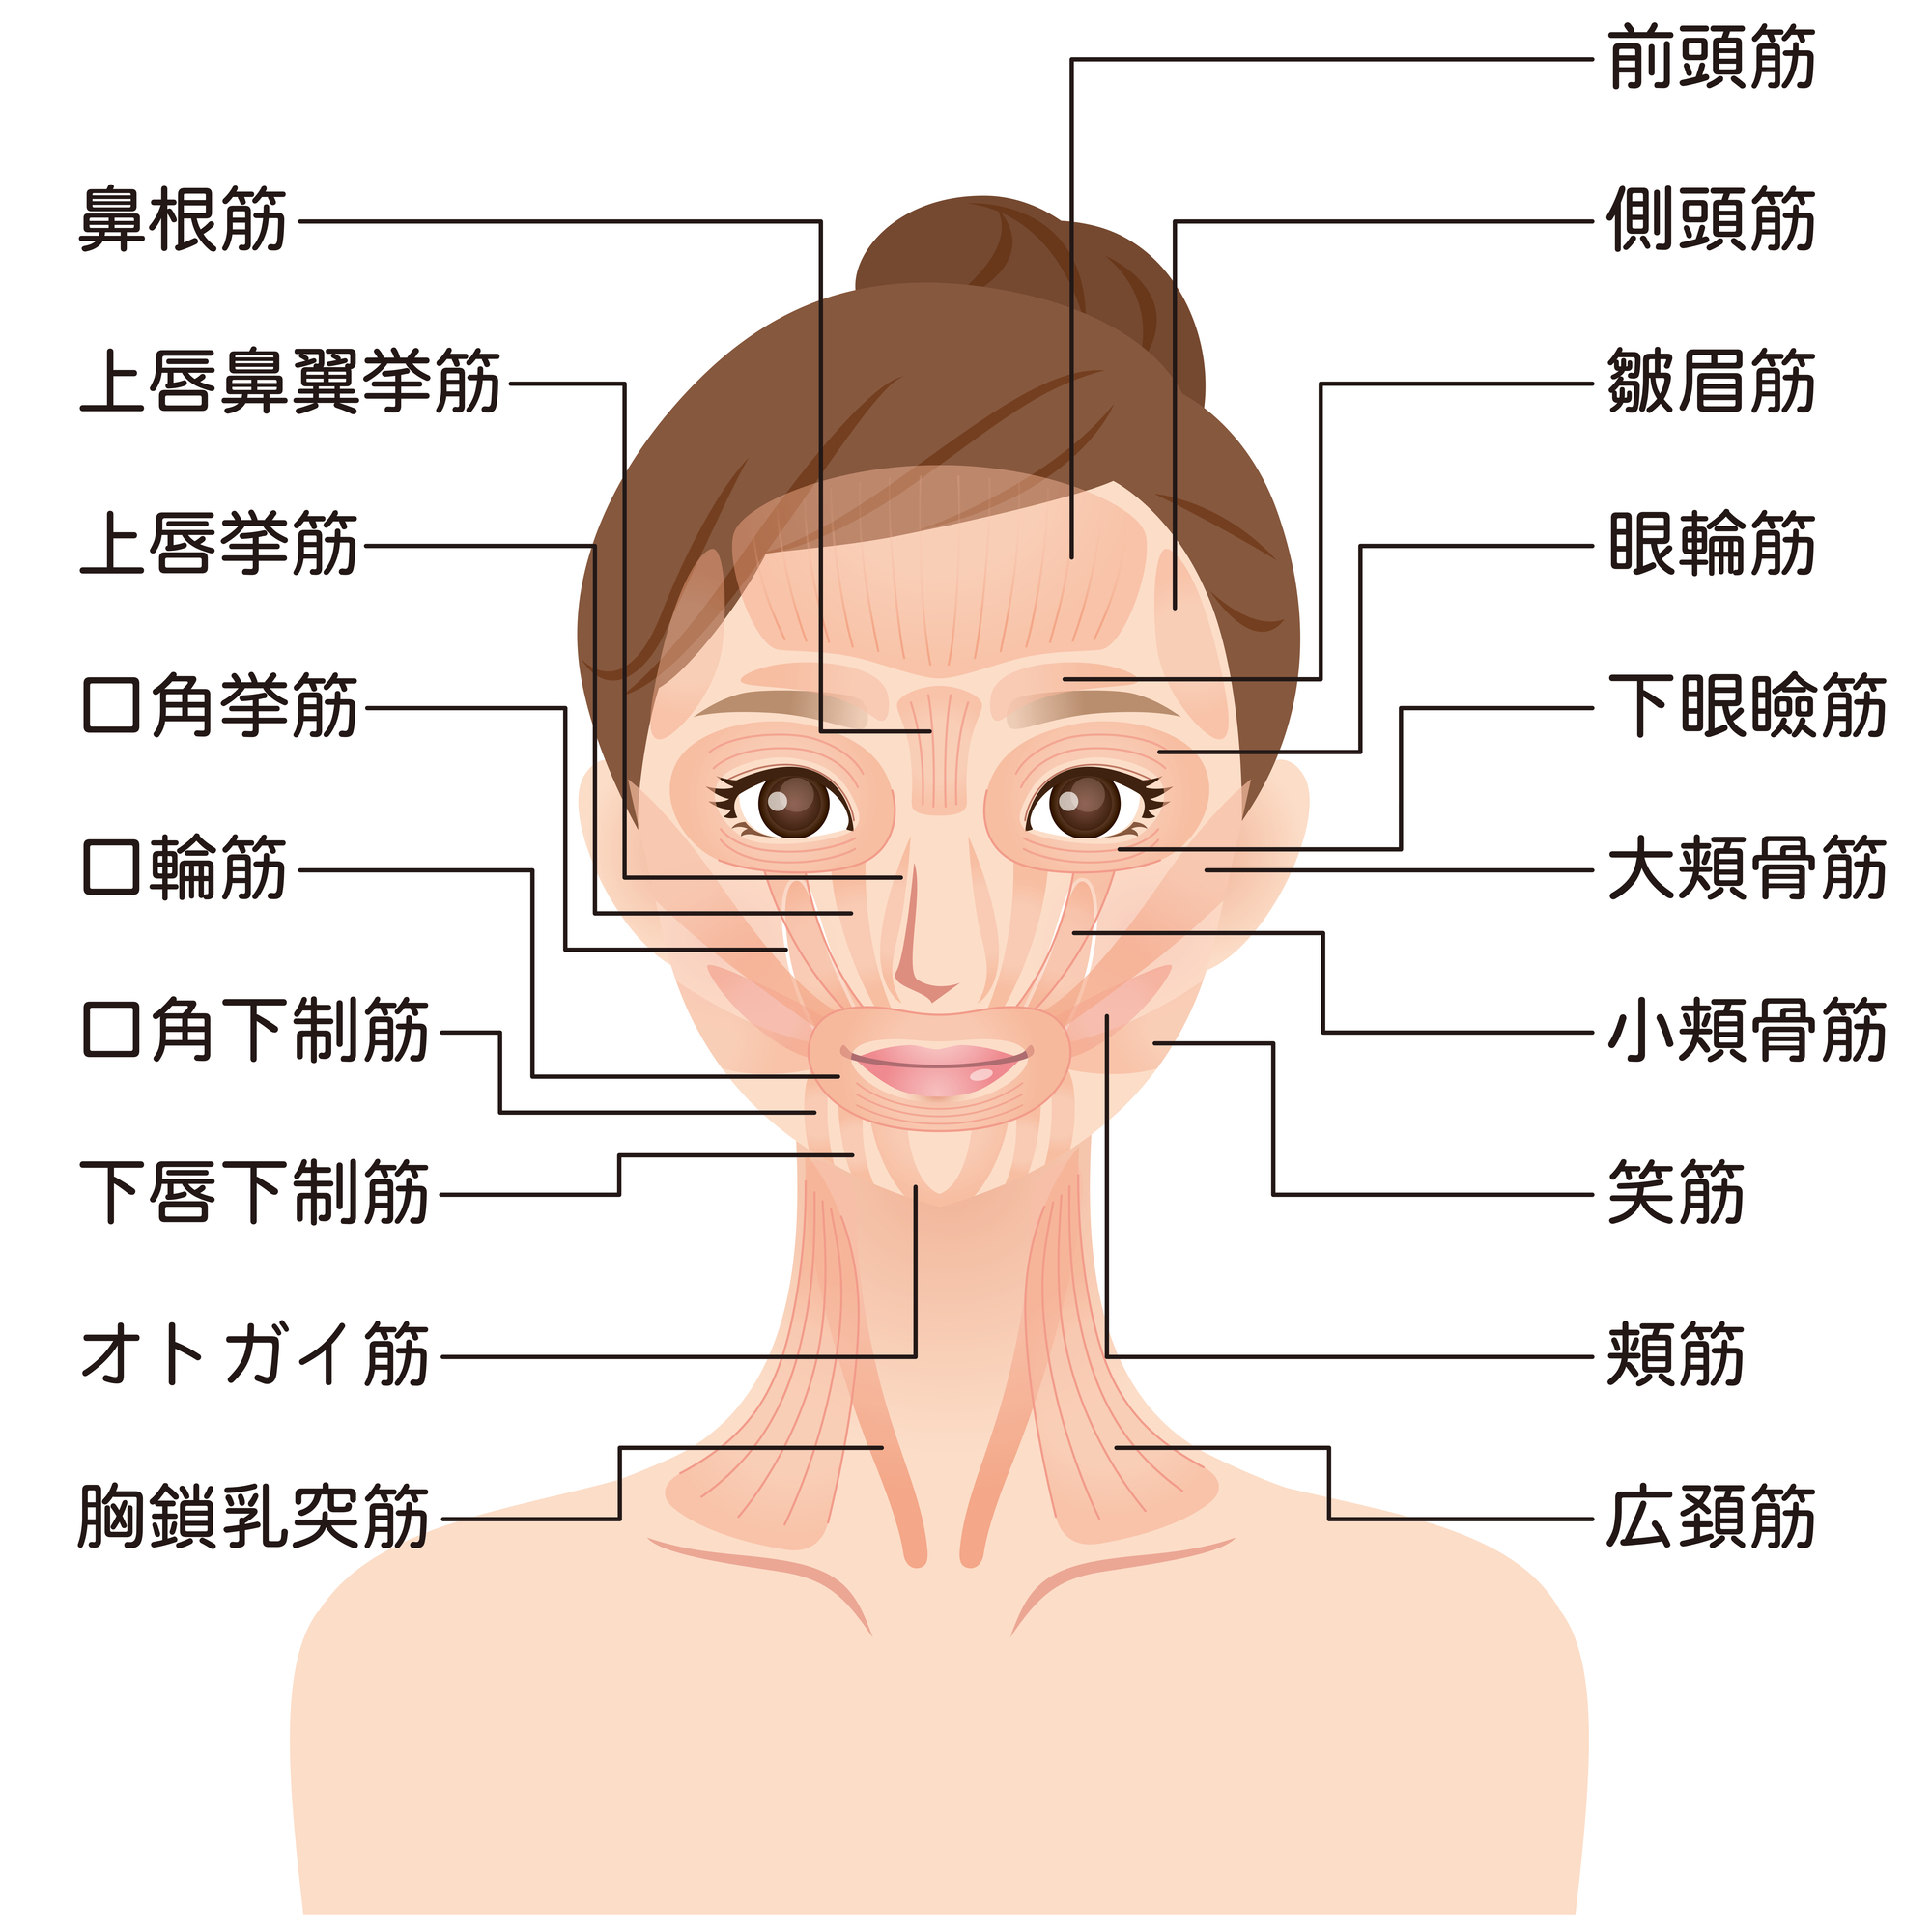

お口の周りの筋肉には、オトガイ筋・顎舌骨筋・口輪筋・頬筋があります。

①オトガイ筋(顎を動かした際に梅干しの種のようやシワが出来る部分)

→顎を押し上げる・下唇を押し上げる・顎先の皮膚を内側・上に引っ張る・口をへの字にする・上唇を突き出す。このような作用があります。

オトガイ筋があることで、あごのたるみを防ぎます。

②顎舌骨筋(顎下の真ん中を通っている部分)

→口腔底をつくる筋肉・飲み込む時に舌を上にあげる。

顎舌骨筋があることで、舌を持ち上げ、口腔底を持ち上げる顎から下のラインをきれいにします。

③口輪筋(口の周りを囲んでいる部分)

→口を閉じる・唇を突き出す・口角をあげる

このような作用があります。

口輪筋があることで、口元を若々しくします。

④頬筋

→口角を外側に引き上げる・頬を歯並びに押し付ける・頬を膨らませる・凹ませる・吸う。などの作用があります。

ほおをきゅっと引き締めます。